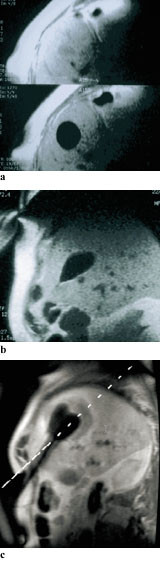

God monitorering er nødvendig for å sikre adekvat frysing av tumor. Slik monitorering må kunne visualisere iskulens lokalisasjon i forhold til tumor i alle plan og slik sikre at hele tumor er fryst, dvs. omgitt av iskulen. Det må også kunne angis om temperaturen har vært lav nok for destruksjon i hele tumorvolumet. Ultralyd, som vanligvis benyttes, tilfredsstiller ikke disse kravene til god monitorering (28). Overgangen mellom fryst/ikke-fryst vev er vanskelig å visualisere langs hele omkretsen av tumor, delvis pga. akustisk skyggedanning på baksiden av iskulen som hindrer innsyn (fig 2) (29). Ultralyd angir heller ikke temperaturfordelingen i iskulen. Destruksjonen av tumorvev blir dermed dårlig kontrollert ved denne monitoreringsmodaliteten.

MR tilfredsstiller kravene til monitorering bedre, idet overgangen fryst/ikke-fryst vev visualiseres klart i alle plan (fig 3) (30). I tillegg har man i eksperimentelle studier vist at man kan estimere temperaturfordelingen i iskulen ved hjelp av MR (fig 4) (31, 32). Tilgjengeligheten av intervensjons-MR er imidlertid problematisk sammenliknet med ultralydteknikk.

Det er vanskelig å monitorere prosedyren ved hjelp av ultralydteknikk. Ett problem er manglende tredimensjonal kontroll av iskulens posisjon i forhold til tumor (fig 2) (29). Dette skyldes delvis akustisk skyggedanning, men også at det kan være vanskelig å posisjonere ultralydproben for undersøkelse i mange plan. MR representerer i denne sammenhengen en forbedring ved at kryolesjonen defineres klart i alle plan, men også her er det rom for videreutvikling. Blant annet vil det være nyttig å fremstille tumors lokalisasjon inne i iskulen. Dette krever metoder der man synkroniserer preoperative MR-bilder av tumor med peroperative bilder av kryolesjonen, siden man for praktiske formål ikke har MR-signaler fra selve kryolesjonen, som fremstår som svart. Ideell plassering av kryoprobene for å kunne danne en iskule optimalt lokalisert i forhold til tumor er også en utfordring.